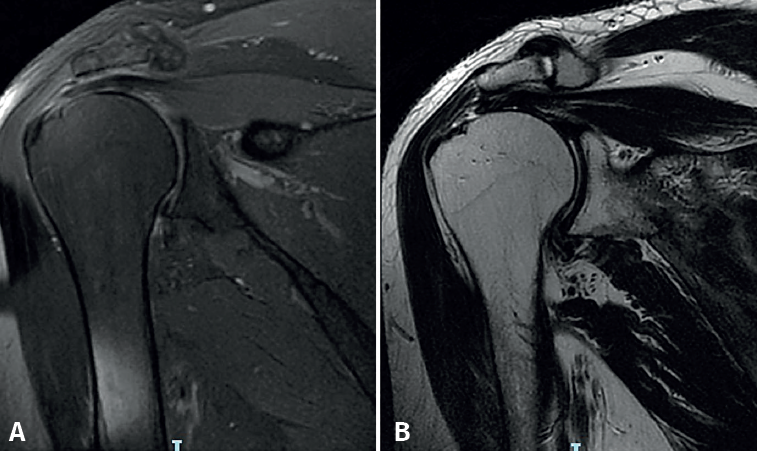

El estudio de resonancia magnética (RM) previo a la cirugía permitió valorar el porcentaje de rotura según los grados de retracción tendinosa establecidos en la clasificación de Patte (Figura 1).

Figura 1. Estudio de resonancia magnética en el caso (hombro izquierdo) seleccionado para esta técnica quirúrgica. Secuencias T1 (A) y T2 (B) que muestran una rotura de tipo 2 de Patte sin atrofia muscular ni infiltración grasa significativas (Goutalier grado 0).